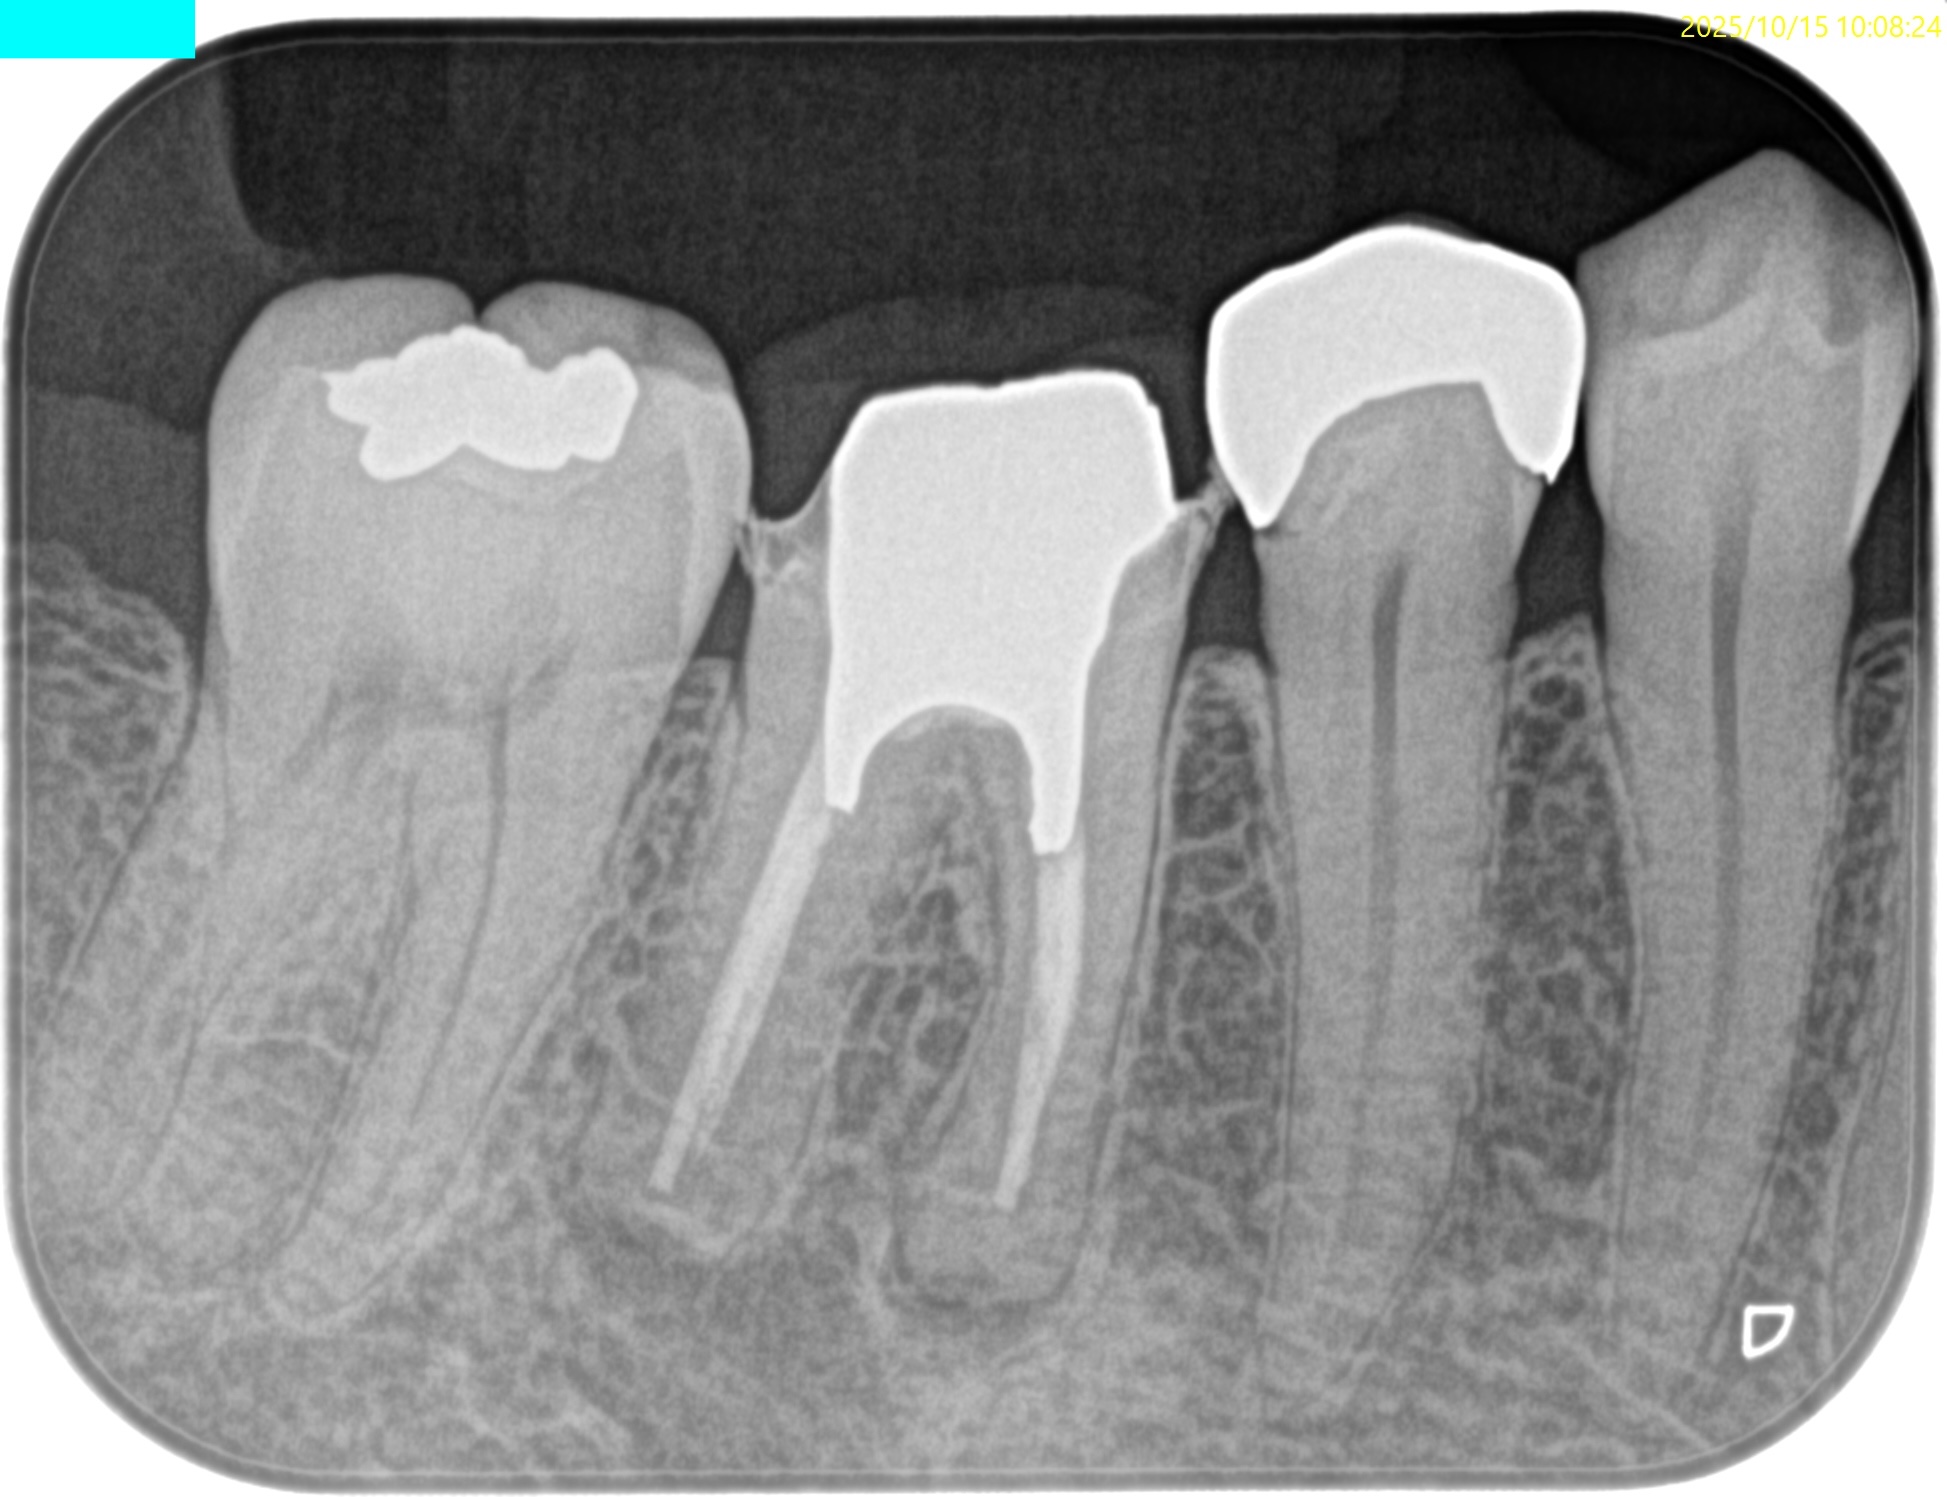

PA(2025.10.15)

Pulp Dx: Previously treated

Periapical Dx: Asymptomatic apical periodontitis

Recommended Tx: Re-RCT+Core build up